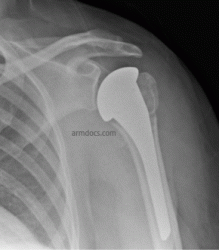

Three months following hemiarthroplasty and tuberosity repair

The operation is performed under a combination of general and regional anaesthesia. The shoulder is exposed, the humeral head (ball fragment) is removed and a metal prosthesis is implanted in the shaft of the humerus. The tuberosities (bone fragments which carry tendon attachments) are realigned and then fixed to the prosthesis and humeral shaft with sutures or cable. The fixation is supplemented with bone grafting using bone from the removed fragment.